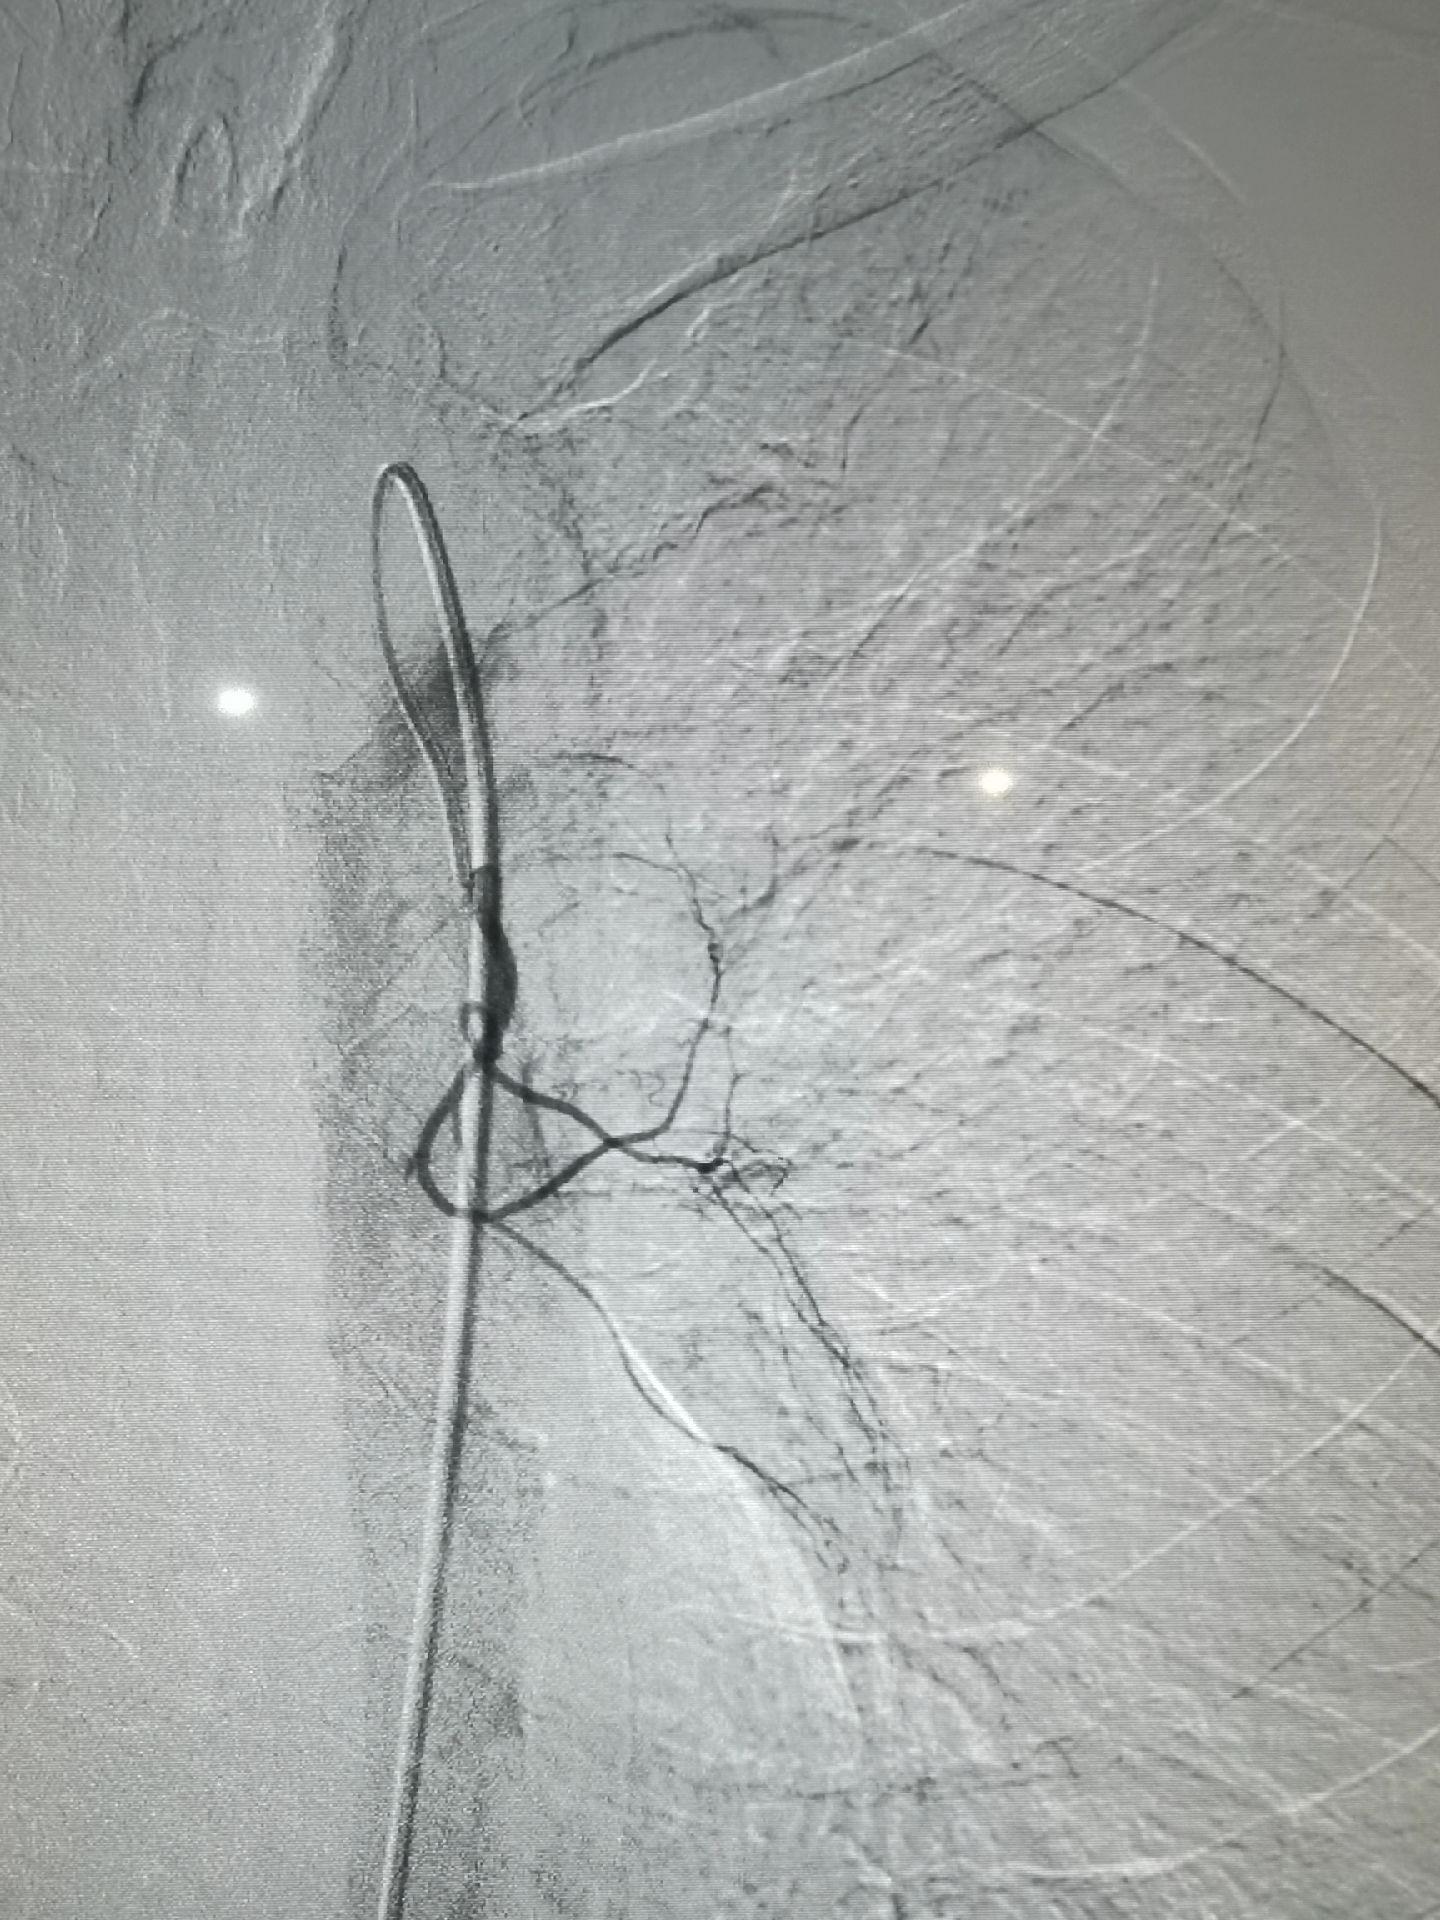

左上肺癌,锁骨上动脉造影,甲状颈干分支供应左上肺癌,反复使用单弯导管无法勾到责任血管,单弯导管热蒸汽成形后成功找到责任血管,微导管超选后CBCT证实肿瘤染色丰富后进行微球栓塞。